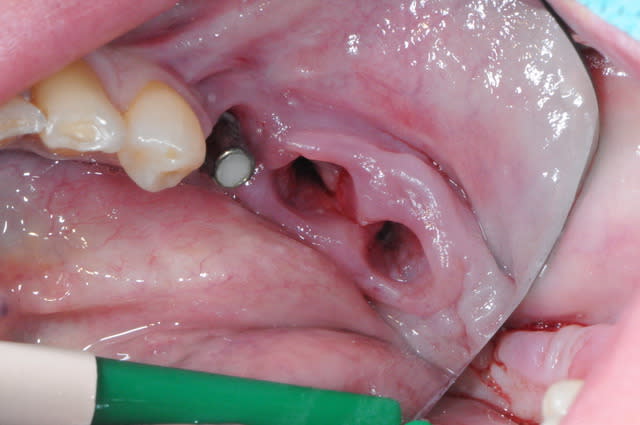

3 aspect (in vivo)

:)

1-2-3 dépose du bridge

facile :) ça vient tout seul.